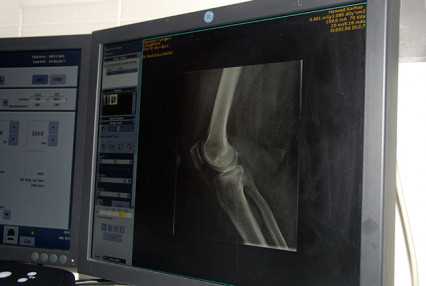

Röntgen- és ultrahang-vizsgálaton valószínűleg már mindenki átesett többször is az életében, a legtöbben pedig a CT-ről és az MR-ről is hallottak már. Ez a négy módszer alkotja a képalkotó diagnosztikát. A Honvédkórházban ezzel a szakterülettel a Radiológiai Osztály foglalkozik.

A Honvédkórház eddig bemutatott részlegei között a Radiológiai Osztály a „kakukktojás”, hiszen itt nincsen fekvő-, csak járóbeteg-ellátás. Persze a fekvőbeteg-ellátásból is kiveszik a részüket, hiszen a más osztályokon gyógyulók képalkotó diagnosztikai vizsgálatait itt végzik.

A Honvédkórház Radiológiai Osztálya egyébként három részlegből áll, három telephelyen található egy-egy, az orvosok és az asszisztensek pedig „forgó rendszerben” dolgoznak. Szerencsére az osztály felszereltsége nagyon jó, a röntgengépek életkora fiatalabb az országos átlagnál. A Róbert Károly körúti telephelyen kettő, a Podmaniczky utcai objektumban pedig egy, nagy teljesítményű CT-berendezés üzemel. Ezeket másfél-két évvel ezelőtt sikerült beszerezniük, s azóta is „maximális kapacitással” működnek. Mindezek mellett a Róbert Károly körúti telephelyen egy nagy teljesítményű MR-készülék is a gyógyítást szolgálja. „Sajnos az MR-vizsgálatokra – az ország más kórházaihoz hasonlóan – nálunk is több hónapos a várólista” – tudjuk meg az osztályvezető főorvostól, aki hangsúlyozza azt is, hogy természetesen a jövőben is várhatóak eszközfejlesztések az osztályon, amelyektől a várakozási idő rövidülését is várják.

A „szakmáról” szólva dr. Riedl Erika elárulja: a képalkotó diagnosztika nagyon sokat és dinamikusan fejlődött az elmúlt évtizedekben. „Régebben csak a hagyományos röntgengépekkel tudtunk dolgozni. Ez egyébként az oka annak, hogy a szakterület a radiológia nevet kapta. Aztán fokozatosan megjelent az ultrahang, aminek ugyan már semmi köze nincsen a röntgensugárzáshoz, de mivel képalkotó diagnosztika, ugyanúgy zömében a radiológusok csinálták” – meséli a főorvosnő, hozzátéve: a műszerek fejlődésének következő fokozata a CT volt, ami visszatért a röntgensugarak használatához. De amíg a hagyományos röntgengépekkel csak 2D-s képet lehetett készíteni, addig a CT egy keresztmetszeti, tehát jóval pontosabb képet ad a vizsgált területről.